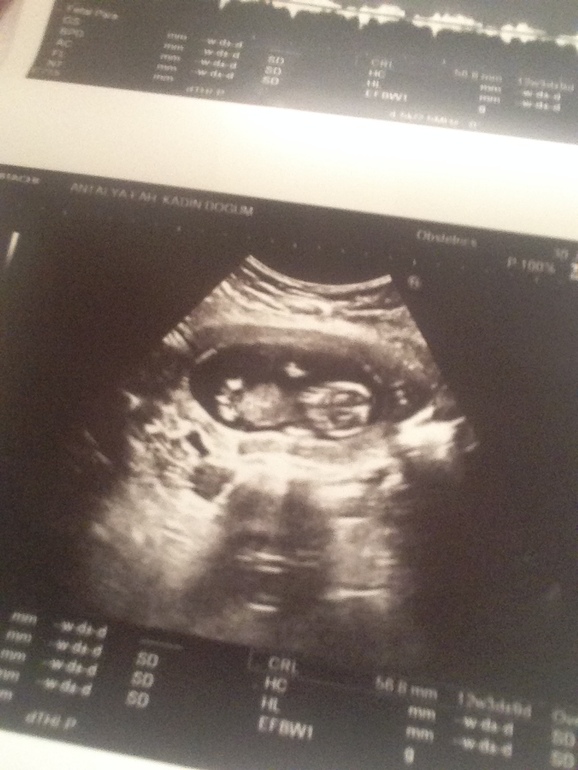

Пол малышаМожно ли по такому снимку предположить кто у нас на первый скрининг только через неделю на фото 12+1 недель

Не то сын, не то дочь. Точно одно из двух. 😁 Главное что не неведомая зверушка, а очертания ребёночка. Рановато утверждать.

С вероятностью в 50% предположить можно.

Но гадание по «бугоркам» тоже не правдоподобно. В 12.6 врач по бугорку предположил мальчика, а на самом деле девочка